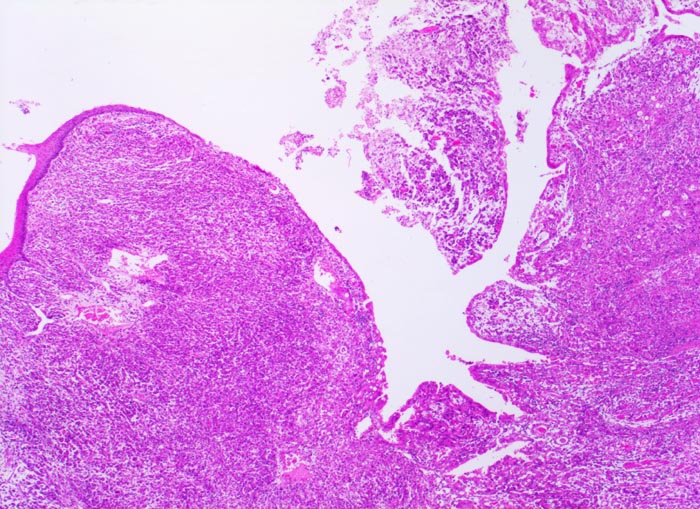

• Gewebsfragment aus gastroösophagealem Übergang.

• Das unscharf begrenzte Karzinom breitet sich diffus in der gesamten Magenwand und in der Ösophaguswand aus bis in des periösophageale und subseröse Fettgewebe.

• Ein Grossteil des Tumorinfiltrats besteht aus einzeln oder in kleinen Gruppen liegenden Zellen mit intrazytoplasmatischen Schleimvakuolen, die teilweise den Kern verdrängen (Siegelringzellen): diffuser Typ des Magenkarzinoms nach Lauren.

• Nur vereinzelt Drüsenbildung.

• Lymphgefässeinbrüche.